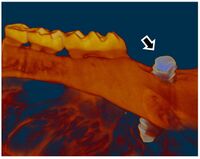

| Research GoalsSkeletal fracture is one of the most prevalent and costly medical issues in the United States, with direct costs exceeding $20 billion annually. In fact, some studies have shown that women over the age of 75 would rather be dead than suffer the consequences of a hip fracture. As a result, the overall goal of the Tomlinson lab is to determine novel mechanisms that augment bone strength and induce the rapid repair of skeletal fractures. In particular, the lab focuses on inflammatory signaling in the skeletal response to mechanical forces and damage using small animal models. The Role of NGF-TrkA Sensory Nerve Signaling in Bone Although sensory nerves are known to be present in mature bone, relatively little is understood about their function in the skeleton, aside from pain. In this project, we are investigating the role of NGF-TrkA signaling in sensory nerves. Nearly all of the nerves in bone express TrkA, the high affinity receptor for nerve growth factor (NGF). Furthermore, sensory nerves blanket the surfaces of bone in a mesh-like network, a privileged location for the acquisition of mechanical signals. Using both in vivo and in vitro methods, we have demonstrated that NGF is robustly expressed by mature osteoblasts in response to non-damaging mechanical loads. Inhibition of NGF-TrkA signaling impairs load-induced bone formation whereas administration of exogenous NGF increases relative bone formation rates. These effects appear to be facilitated through altered Wnt/β-Catenin signaling, which we are currently investigating by using mice which lack NGF in the osteoprogenitor and osteoblast lineages. In addition, we have identified a compound which may provide long-term activation of TrkA to increase load-induced bone formation without the painful side effects of NGF. 1. Tomlinson RE, Li Z, Zhang Q, Goh BC, Li Z, Thorek DL, Rajbhandari L, Brushart TM, Minichiello L, Zhou F, Venkatesan A, Clemens TL. “NGF-TrkA Sensory Nerve Signaling Coordinates Vascularization and Ossification of Bone”, Cell Reports 2016; 16(10):2723-35. PMID: 27568565. PMCID: PMC5014649 2. Tomlinson RE, Li Z, Li Z, Minichiello L, Riddle RC, Venkatesan A, Clemens TL. “NGF-TrkA Signaling in Sensory Nerves is Required for Skeletal Adaptation to Mechanical Loads in Mice”, Proceedings of the National Academy of Sciences 2017; 114(18):E3632-E3641. PMID: 28416686. PMCID: PMC5422802 3. Li Z, Meyers CA, Chang L, Lee S, Li Z, Tomlinson R, Hoke A, Clemens TL, James AW. “Fracture repair requires TrkA signaling by skeletal sensory nerves”, Journal of Clinical Investigation 2019 Dec 2;129(12):5137-5150. PMCID: PMC6877307. 4. Fioravanti G, Hua PQ, Tomlinson RE. “The TrkA agonist gambogic amide augments skeletal adaptation to mechanical loading”, Bone 2021 Jun;147:115908. PMCID: PMC8097708. NSAIDs in Stress Fracture Risk and Repair Non-steroidal anti-inflammatory drugs (NSAIDs) are the most commonly consumed medication in the world, with over 30 million daily users in the United States alone. NSAIDs are effective in reducing pain and inflammation by preventing the synthesis of prostaglandin E2 (PGE2) through the blockade of the cyclooxygenase (COX) enzyme isoforms, COX1 and COX2. However, PGE2 is part of an inflammatory signaling pathway that is known to be critical for load-induced bone formation. In collaboration with our partners at the US Army Research Institute of Environmental Medicine and the Rothman Institute, we have identified a clear link between NSAID usage and stress fracture susceptibility. Furthermore, we have observed in mice that NSAIDs may increase stress fracture risk through two independent mechanisms – diminished load-induced bone formation and decreased bone toughness. In addition, we have identified NSAIDs which can provide analgesia without affecting stress fracture risk or repair. We are currently analyzing the mechanisms by which NSAIDs affect the skeleton, with the aim of uncovering novel therapeutic targets for relieving musculoskeletal pain without affecting bone health. 1. Park J, Fertala A, Tomlinson RE. “Naproxen impairs load-induced bone formation, reduces bone toughness, and diminishes woven bone formation following stress fracture in mice.” Bone 2019; 124:22-32. PMID: 30998998 2. Johnston TE, Dempsey C, Gilman F, Tomlinson R, Jacketti A, Close J. “Physiological Factors of Female Runners With and Without Stress Fracture Histories: A Pilot Study.” Sports Health 2020;12(4):334-340. PMID: 32525466 3. Staab JS, Kolb AL, Tomlinson RE, Pajevic PD, Matheny RW, Hughes JM. “Emerging evidence that adaptive bone formation inhibition by non-steroidal anti-inflammatory drugs increases stress fracture risk”, Experimental Biology and Medicine 2021; Feb 27. PMID: 33641442 NSAIDs in Dental Implant Osseointegration The use of dental implants has transformed the practice of dentistry over the last few decades. The success of this procedure relies on osseointegration, the process by which bone forms a structural and functional connection with the implant over a period of weeks to months. A significant portion of implants fail to osseointegrate, requiring additional surgical intervention. As a result, identifying factors that delay or prevent the osseointegration of dental implants is a top research priority. We hypothesize that use of NSAIDs in the immediate post-operative period may inhibit osseointegration of dental implants. This hypothesis may help explain idiopathic early failure of dental implants, since standard post-operative care often includes immediate and continuous use of high-dose NSAIDs. To directly test our hypothesis, we have assembled a research team of oral surgeons and orthopaedic basic scientists to generate quantitative data from newly placed dental implants as well as analyze bone tissue to ascertain the events that lead to early implant failure. This project is supported by an Osteo Science Foundation grant, in collaboration with our partners in Oral and Maxillofacial Surgery. Bioprinting Vascularized Bone Grafts The main cause of large bone graft failure is poor vascularization which leads to inner graft necrosis. Although this issue has been recognized for some time, developing bone grafts with adequate vascular function has proven to be a difficult problem to address and has prevented the widespread clinical use of engineered bone constructs. In this research area, we utilize 3D bioprinting to generate vascularized bone graft using patient-specific imaging data. First, we are developing a new computational tools to provide semi-automated generation of vascular structures within volume generated from standard clinical imaging. Next, we are optimizing the parameters used for extrusion bioprinting to improve outcomes and reproducibility using a type II fuzzy system. Our ultimate goal is to use bioprinting to generate patient-specific vascularized bone grafts for repair of carpal bones and other small bones with complex geometry and articulating surfaces. 1. Sedigh A, DiPiero D, Shine KM, Tomlinson RE. "Enhancing Precision in Bioprinting Utilizing Fuzzy Systems", Bioprinting. 2022 March. doi: 10.1016/j.bprint.2021.e00190. 2. Morrison DG, Tomlinson RE. “Leveraging advancements in tissue engineering for bioprinting dental tissues”, Bioprinting. 2021 Aug;23. doi: 10.1016/j.bprint.2021.e00153. Epub 2021 Jun 13. PubMed PMID: 34268456; PubMed Central PMCID: PMC8276871. 3. Sedigh A, Akbarzadeh-T MR, Tomlinson RE. "Comparison of Type-1 and Type-2 Fuzzy Systems for Mineralization of Bioprinted Bone", bioRxiv. 2021 March. doi: 10.1101/2021.03.31.437908. 4. Sedigh A, Tulipan JE, Rivlin MR, Tomlinson RE. "Utilizing Q-Learning to Generate 3D Vascular Networks for Bioprinting Bone", bioRxiv. 2020 October. doi: 10.1101/2020.10.08.331611. Other Research AreasCheck out our Publications. |